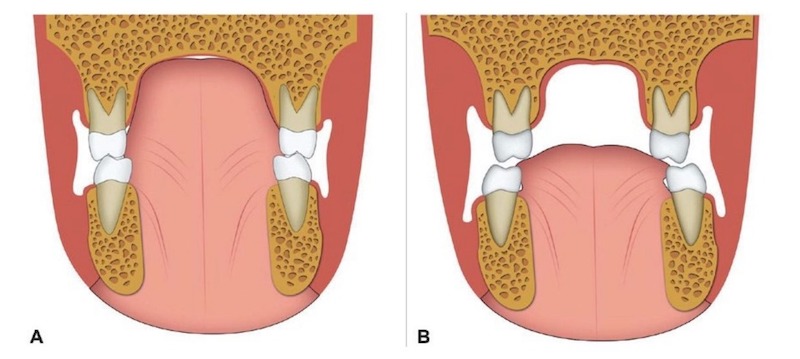

首先,牙齒的外側是我們的臉頰,內側是舌頭肌肉,這兩者之間會形成力的平衡,正常情況下力的平衡會讓牙齒牙弓生長成一個碗公或U的形狀,一個弧形的形狀是力平衡的結果。

左圖是舌頭正常休息位置,輕輕頂在上顎,牙齒內側舌頭和外側臉頰肌肉形成平衡;右圖是舌頭位置太低,導致上牙弓容易坍縮,變成較狹窄的形狀。

左圖為標準的力平衡,牙弓及齒列也會順著力量自然形成U字型。中間圖表示通常若舌頭位置不恰當,或力量較低、外側力較大時,就容易形成如右圖的狹窄型牙弓,而門牙則容易被推擠往前飛去而形成暴牙。

由此可知,力的平衡一旦少了外側力,牙齒就會往外;反之少了內側力則會往內推擠,造成牙弓狹窄,而當牙弓變成V字型時,門牙就容易外飛。